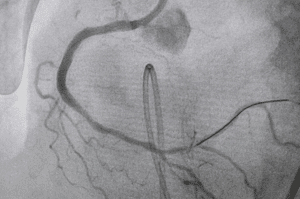

Seldinger procedure which involves placing a catheter via the common femoral artery which was utilized for digital subtraction angiography and selective arterial embolization under local anesthesia.Â

The process involved is three phases starting with Digital Subtraction Angiography to create a vascular map of the PT anatomical region.Â

The second phase involved selective catheterizations using a coaxial catheter system which is followed by embolization of lesion-supplying vessels by Digital Subtraction Angiography to confirm the occlusion effectiveness and assess any remaining pathological blood flow.Â

After the procedure was completed a post-procedure PT and Digital Subtraction Angiography was performed to evaluate the occlusion efficacy.Â